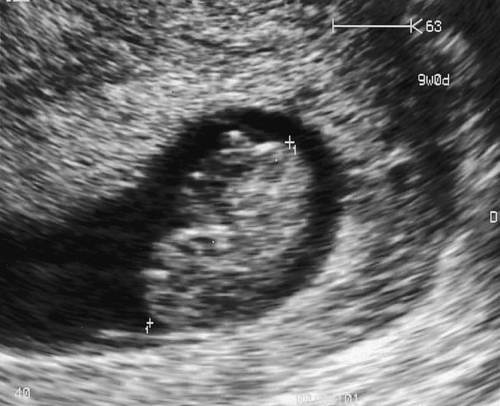

The prognosis is good and the parents can be offered reasonable reassurance (Fig. 10.2). If there are recurrent bleeds, however, the pregnancy may be considered as high risk.

Fig. 10.2An intrauterine 22 mm fetal pole, consistent with 9 weeks’ gestation.

Fetal heart activity was seen.